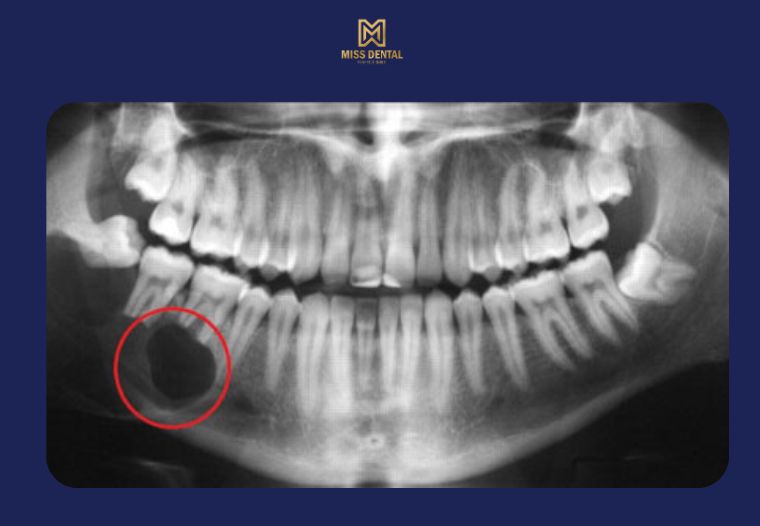

Nang chân răng (hay còn gọi là nang quanh chóp răng) là một dạng tổn thương dạng túi, chứa dịch hoặc mô hoại tử, hình thành ở phần chóp chân răng, thường do viêm tủy răng kéo dài không được điều trị triệt để. Nang này phát triển âm thầm trong xương hàm và có thể tồn tại lâu năm mà không gây triệu chứng rõ ràng.

Ở giai đoạn đầu, nang chân răng thường không gây đau nhức, khiến người bệnh chủ quan. Tuy nhiên, theo thời gian, nang sẽ phát triển lớn dần, gây tiêu xương, ảnh hưởng đến các răng lân cận, thậm chí lan sang các cấu trúc quan trọng như xoang hàm, dây thần kinh hàm dưới.

Tiêu xương hàm: Nang lớn có thể phá hủy xương ổ răng, làm răng lung lay hoặc mất răng.